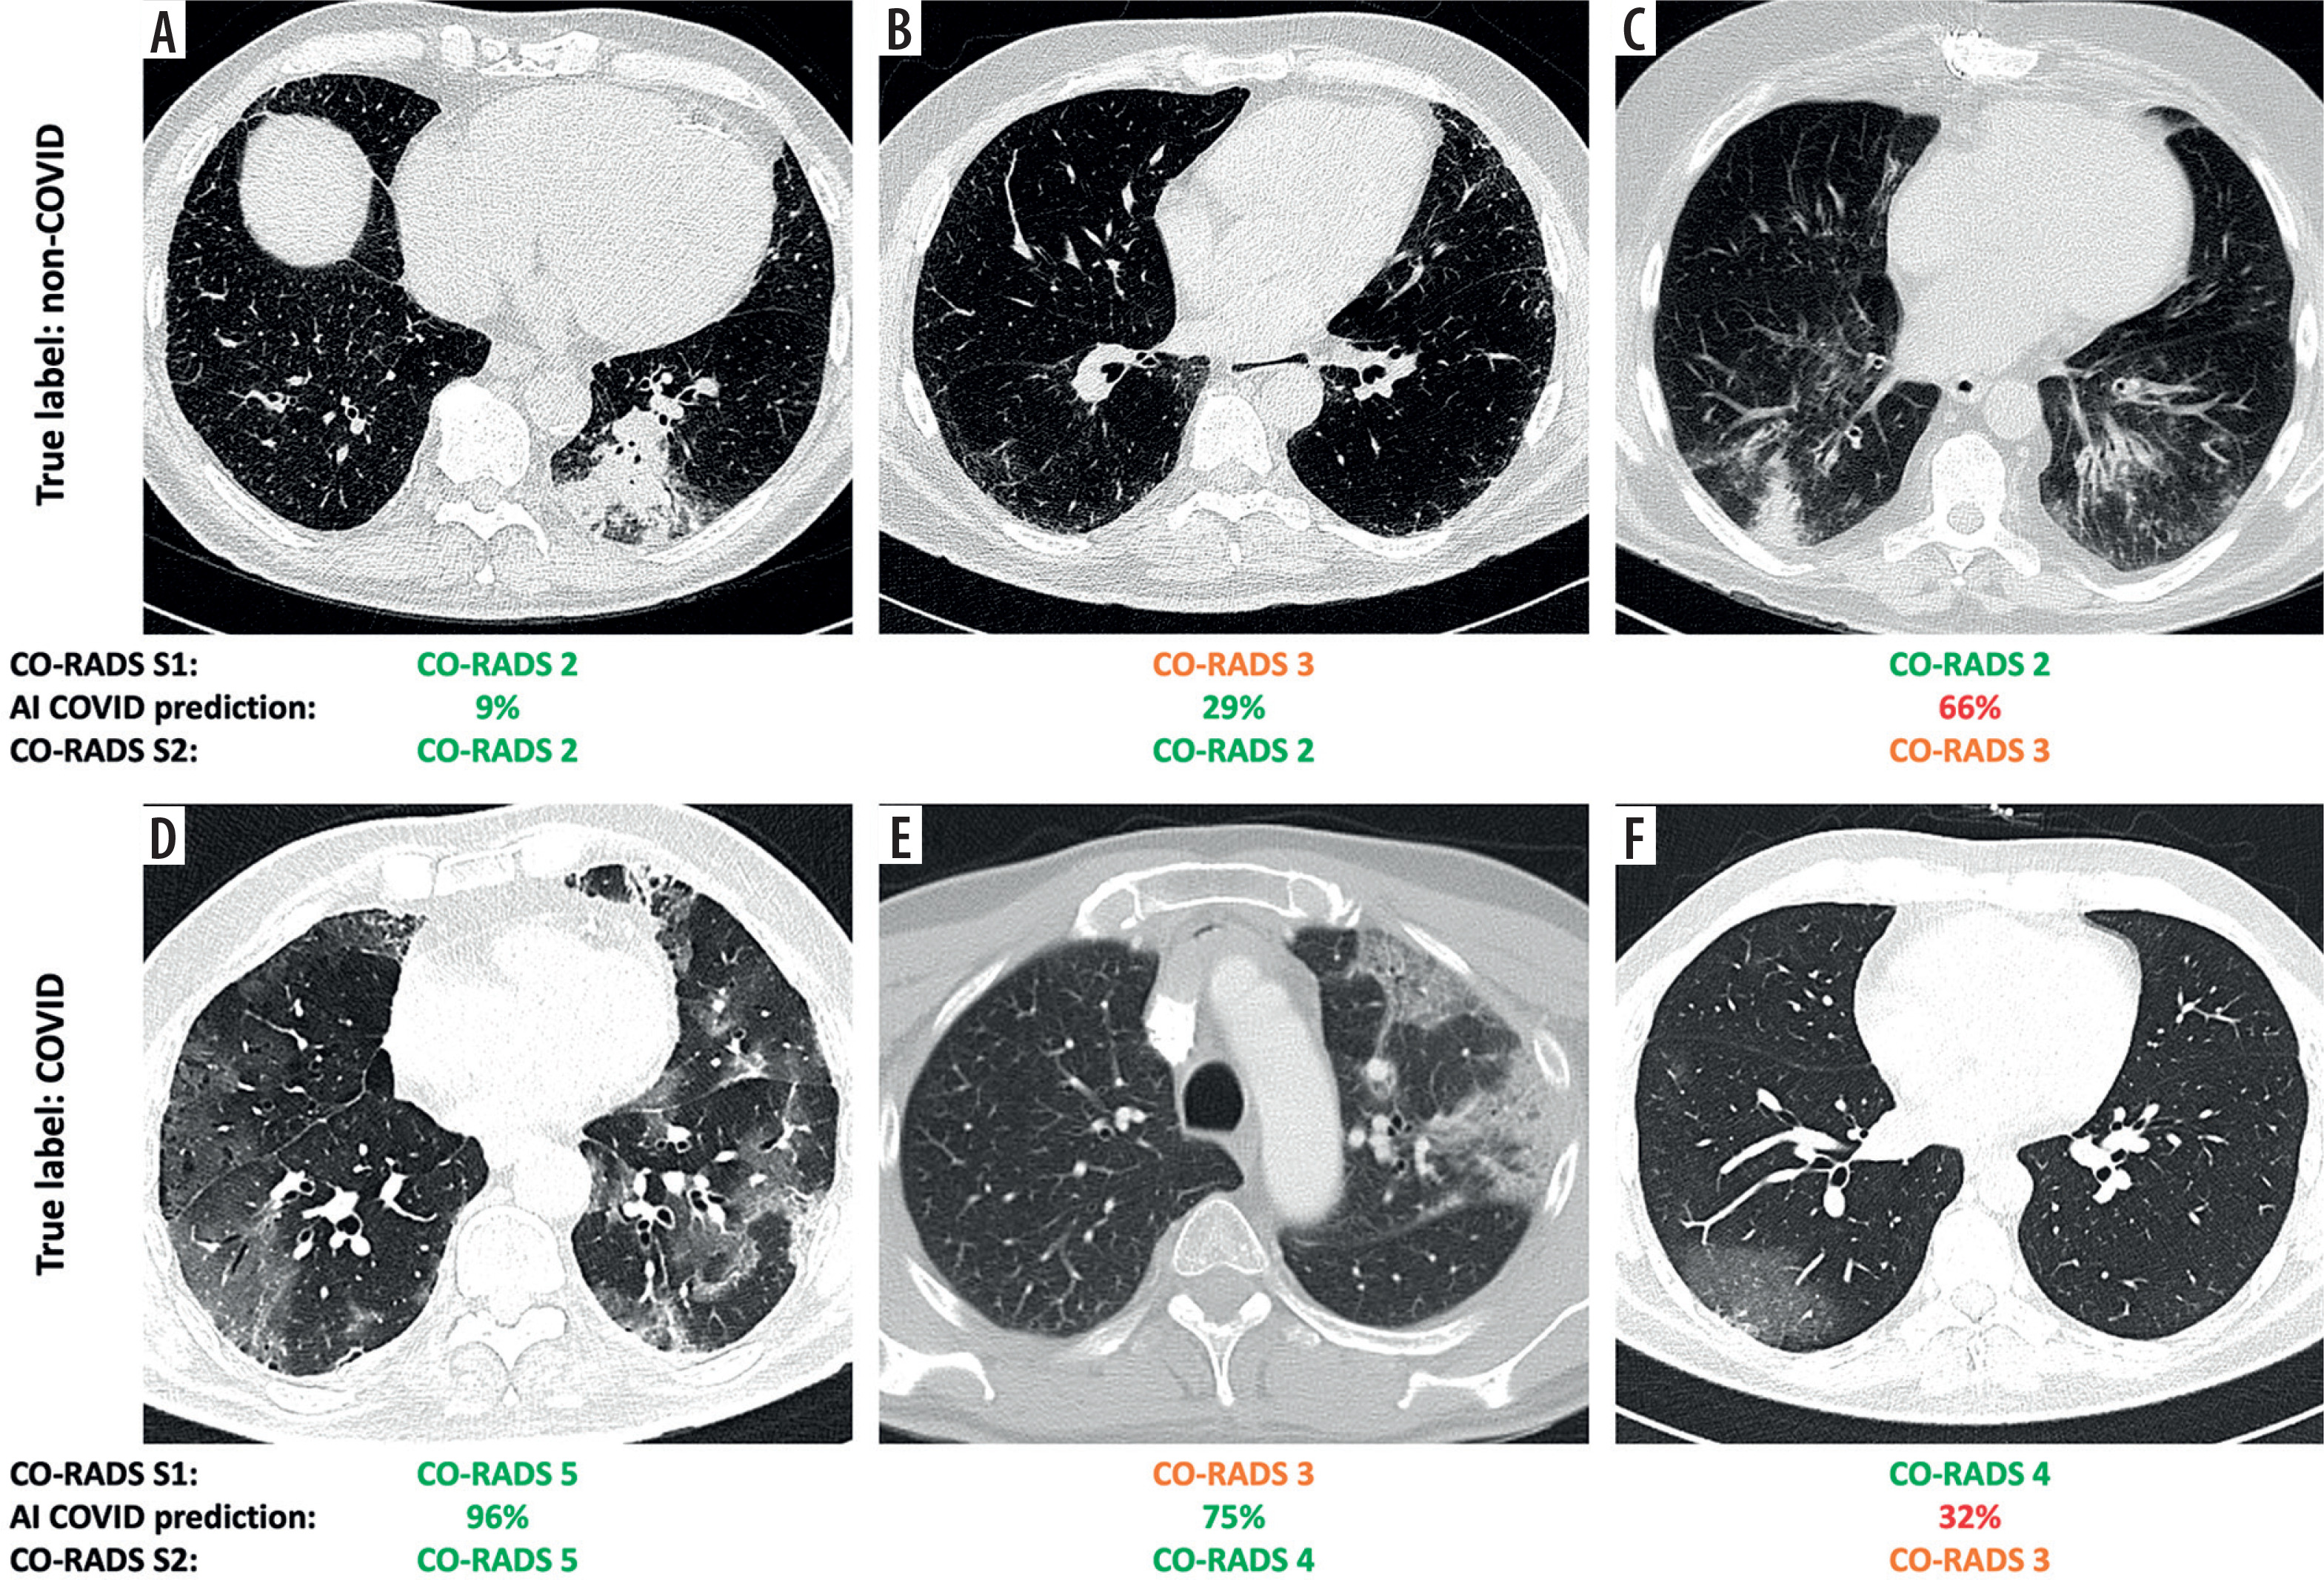

Upon reviewing the AI output in S2 with default approach, Reader 1 modified the CO-RADS score in 47/220 cases (21%), Reader 2 in 54/220 cases (25%), and Reader 3 in 16/220 cases (7%). From a clinical perspective, these changes in CO-RADS scores translated into an actual shift in classification between COVID-19, non-COVID-19, or equivocal case in 35/220 (16%) for Reader 1, 26/220 (12%) for Reader 2, and 15/220 (7%) for Reader 3. Notably, when the radiologists were confident in S1 diagnosis (i.e. CO-RADS ≠ 3), a classification change in S2 occurred in 7% of cases, on average. This prevented an incorrect diagnosis in 45% of cases, but in the remaining 55% a correct classification was missed. When considering only the score variations when a CO-RADS = 3 was initially assigned, corresponding to the selective approach, changes were observed in 14/220 (6%) for Reader 1, 14/220 (6%) for Reader 2, and 6/220 (3%) cases for Reader 3. In such a setting, the radiologists moved from an uncertain diagnosis (i.e. CO-RADS = 3) to a correct classification in 85% of the cases, on average. Some relevant examples are shown in Figure 2.

Figure 2

Representative cases illustrating different outcomes in the classification of respiratory viral pneumonias with the aid of an artificial intelligence (AI)-based classifier. For each case, the radiologist-assigned COVID-19 Reporting and Data System (CO-RADS) score is reported before (S1) and after (S2) reviewing the AI-generated COVID-19 probability. In cases where initial uncertainty (S1) was present, AI support often helped resolve the doubt. Conversely, in initially confident assessments, AI input occasionally introduced new uncertainty. The examples shown include pneumonias caused by (A) rhinovirus, (B) human coronavirus NL63 (HCoV-NL63), (C) parainfluenza virus type 3 (PIV3), and (D-F) SARS-CoV-2 infection